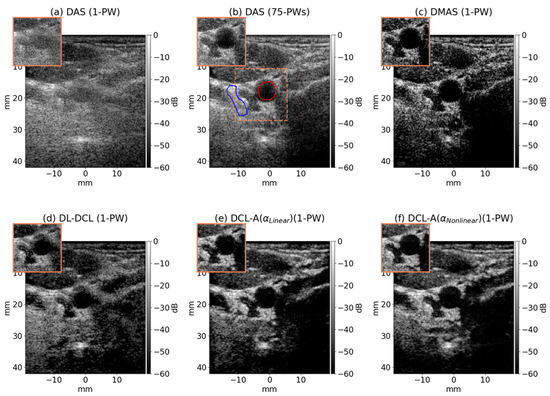

DCL-A: An Unsupervised Ultrasound Beamforming Framework with Adaptive Deep Coherence Loss for Single Plane Wave Imaging

by Taejin Kim, Seongbin Hwang, Minho Song and Jinbum Kang

Diagnostics 2025, 15(24), 3193; https://doi.org/10.3390/diagnostics15243193 - 14 Dec 2025

Background/Objectives: Single plane wave imaging (SPWI) offers ultrafast acquisition rates suitable for real-time ultrasound imaging applications; however, its image quality is compromised by beamforming artifacts such as sidelobe and grating lobe interferences. Methods: In this paper, we introduce an unsupervised beamforming [...] Read more.

Background/Objectives: Single plane wave imaging (SPWI) offers ultrafast acquisition rates suitable for real-time ultrasound imaging applications; however, its image quality is compromised by beamforming artifacts such as sidelobe and grating lobe interferences. Methods: In this paper, we introduce an unsupervised beamforming framework based on adaptive deep coherence loss (DCL-A), which employs linear (αlinear) or nonlinear weighting (αnonlinear) within the coherence loss function to enhance the artifact suppression and improve overall image quality. During training, the adaptive weight (α) is determined by the angular distance between the input and target PW frames, assigning lower α values for smaller distances and higher α values for larger distances. Therefore, this adaptability enables the method to surpass conventional DCL (no weighting) by emphasizing the different spatial correlation characteristics of mainlobe and sidelobe signals. To assess the performance of the proposed method, we trained and validated the network using publicly available datasets, including simulation, phantom and in vivo images. Results: In the simulation and phantom studies, the DCL-A with αnonlinear outperformed the comparison methods (i.e., conventional DCL and DCL-A with αlinear) in terms of peak range sidelobe level (PRSLL), achieving 7 dB and 14 dB greater sidelobe suppression, respectively, while maintaining a comparable full width at half maximum (FWHM). In the in vivo study, it achieved the highest contrast resolution among the comparison methods, yielding 2% and 3% improvements in generalized contrast-to-noise ratio (gCNR), respectively. Conclusions: These results demonstrate that the proposed deep learning-based beamforming framework can significantly enhance SPWI image quality without compromising frame rate, indicating promising potential for high-speed, high-resolution clinical applications such as cardiac assessment and real-time interventional guidance. Full article